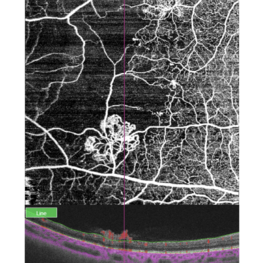

Retinal neovascularization

Feb 28 2023 by Nassim Alejandro Abreu Arbaje, MD

OCT and OCTa of a diabetic patient with severe PDR, showing the anatomical location and blood flow of neovessels

Photographer: Nassim Abreu, Centro de Oftalmologia y Glaucoma

Imaging device: Topcon Triton Plus

Condition/keywords: neovascularization (NV), OCT, OCT Angiography, PDR